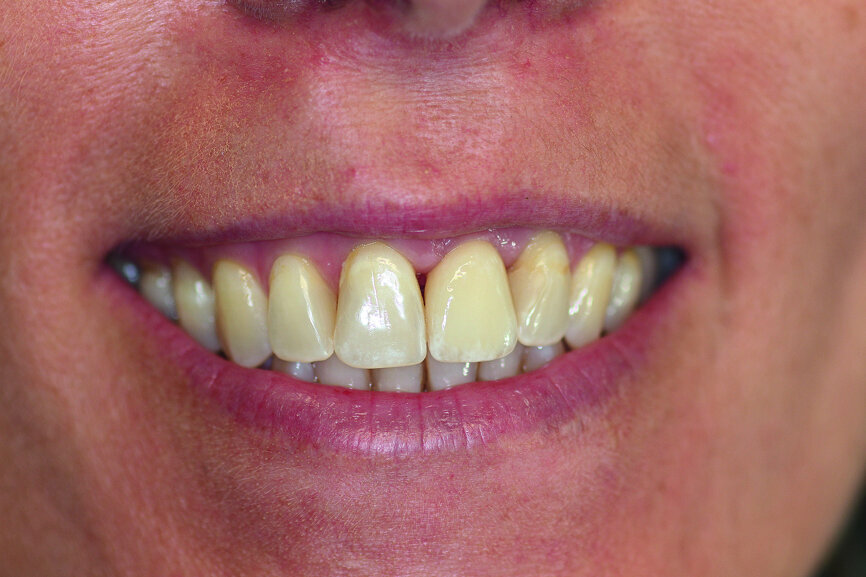

Fig. 11: The final result.

Fig. 12a: Clinical situation at the examinations after a) six and b) 12 months.

Fig. 12b: Clinical situation at the examinations after a) six and b) 12 months.

A provisional crown made of GRADIA (GC), a microceramic composite, was fabricated to achieve optimum contouring of the marginal gingiva in the highly aesthetic zone. A PEEK abutment (ZERAMEX Provisional RB; 180-day maximum period of wear), with a screw (maximum torque of 15 Ncm), acted as the base for the long-term temporary restoration (Figs. 8a & b). After eight weeks and adjusting the long-term temporary restoration in the basal area twice to optimise the emergence profile, the definitive zirconia crown (Ceramill substructure, Amann Girrbach; Creation veneer) was fixed to the customised abutment made of alumina-toughened zirconia (Figs. 9 & 10). After exact positioning (checked by probing or by taking a radiograph) the abutment is firmly fixed by utilising the VICARBO screw which is part of the ZERAMEX system. This unique screw made of carbon fibre-reinforced high-performance polymer is tightened to a torque of 25 Ncm. The final result is shown in Figure 11. The examinations after six and 12 months found no irritation of the soft tissue, and the BOI test was negative. The pink aesthetic score according to Fürhauser was 12 out of a maximum of 14 points (Figs. 12a & b).15 The process of peri-implant bone remodelling was of particular interest. Examinations were performed with periapical radiographs (right angle technique) and DBSWIN software (Dürr Dental).